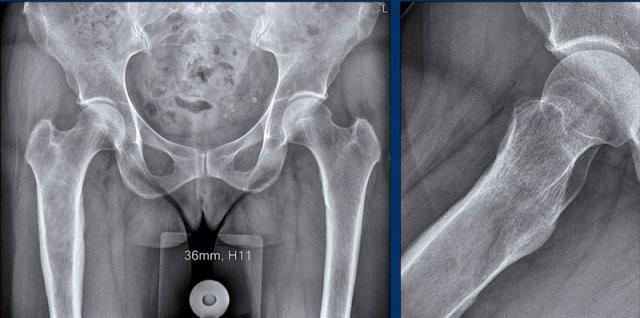

Hình ảnh

Phim X-quang cho thấy một khối u lớn ở thân xương đùi với hình ảnh vôi hóa dạng bỏng ngô điển hình ở phần xa và thành phần tiêu xương nhiều hơn ở phần gần.

Hình ảnh phóng đại chi tiết ở tư thế nghiêng cho thấy khối u xâm lấn vỏ xương và nguy cơ cao gãy xương bệnh lý.

Phần đuôi của khối u có hình ảnh giống u sụn không điển hình (ACT) với hiện tượng lõm vỏ xương khu trú, trong khi phần đầu có hình ảnh giống u sụn ác tính độ cao (CS độ cao).

Kết luận

Đây là hình ảnh điển hình của sarcoma sụn phản biệt hóa, với một phần có biểu hiện như khối u sụn độ thấp đến trung bình với sự chuyển tiếp đột ngột sang thành phần sarcoma độ cao (đôi khi không có nguồn gốc sụn).

Phân nhóm này

thường gặp ở người lớn tuổi.

Tỷ lệ sống còn toàn bộ của sarcoma sụn phân hóa kém rất thấp so với sarcoma sụn độ II và độ III, do bệnh nhân thường đã có di căn phổi và xương tại thời điểm chẩn đoán.